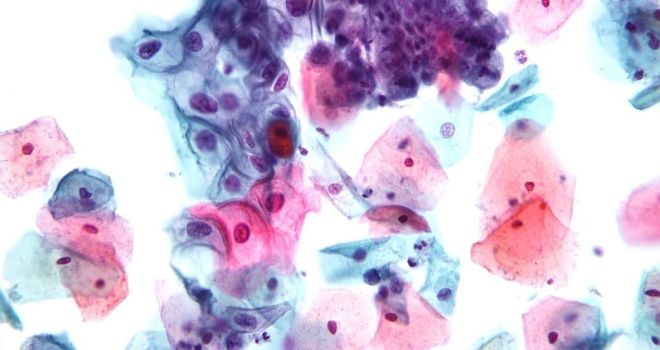

Хламидиоз считается одной из самых распространенных венерических болезней. Сложность заключается в том, что патология долго не проявляется, в 80% процесс проходит без каких-либо симптомов.

При выявлении хламидиоза обязательно в лечебных целях назначают антибактериальные препараты. Но бороться с возбудителями данной инфекции сложно, так как весь жизненный цикл хламидий проходит в клетках организма. Бактерии получают энергию и размножаются внутри клеточных структур. Из-за этого от них сложно избавиться, ведь оболочки клеток надежно защищают бактерии от влияния противомикробных средств.